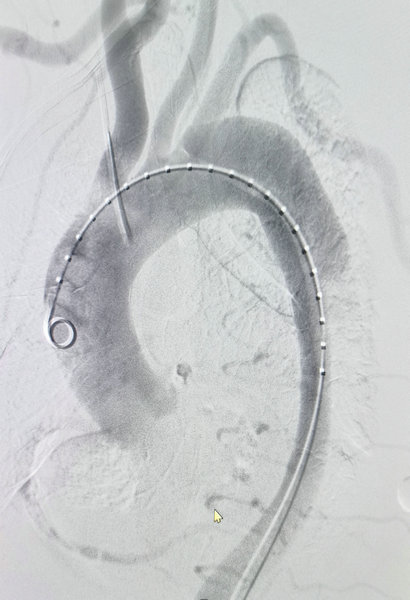

血管外科王颖主任为患者行胸主动脉腔内隔绝联合左侧颈总动脉支架植入术

术中造影显示破口较大真腔受压明显

造影显示主动脉夹层形成